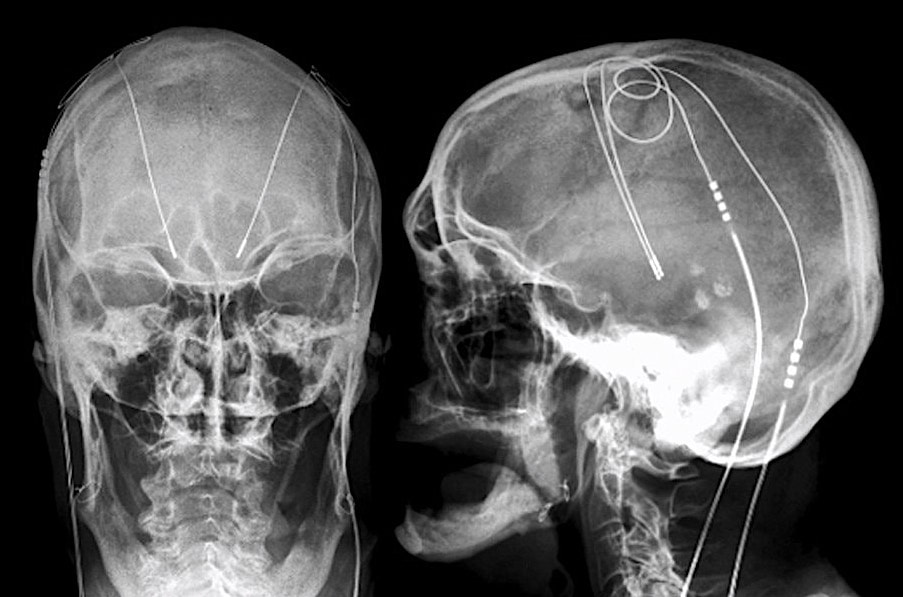

Parkinson's disease brain stimulation electrodes, Xray Stock Image C040/3219 Science Electrodes Brain Stimulation It treats movement disorders, mental health. The electricity can be given directly through electrodes. Deep brain stimulation (dbs) is a neurosurgical procedure that uses implanted electrodes and electrical stimulation to treat movement disorders associated with parkinson’s disease (pd), essential tremor, dystonia and other neurological conditions. Deep brain stimulation (dbs) is an elective surgical procedure in which electrodes are implanted into. Electrodes Brain Stimulation.

Parkinson's disease brain stimulation electrodes Stock Image C040/3229 Science Photo Library Electrodes Brain Stimulation It treats movement disorders, mental health. Deep brain stimulation is a treatment that delivers an electrical current directly into your brain. Deep brain stimulation (dbs) is an elective surgical procedure in which electrodes are implanted into certain brain areas. Electrical brain stimulation (ebs), also referred to as focal brain stimulation (fbs), is a form of electrotherapy used as a technique. Electrodes Brain Stimulation.

Parkinson's Disease Brain Stimulation Electrodes Photograph by Zephyr/science Photo Library Pixels Electrodes Brain Stimulation Deep brain stimulation (dbs) is a neurosurgical procedure that uses implanted electrodes and electrical stimulation to treat movement disorders associated with parkinson’s disease (pd), essential tremor, dystonia and other neurological conditions. Deep brain stimulation (dbs) is an elective surgical procedure in which electrodes are implanted into certain brain areas. The electricity can be given directly through electrodes. Brain stimulation therapies. Electrodes Brain Stimulation.